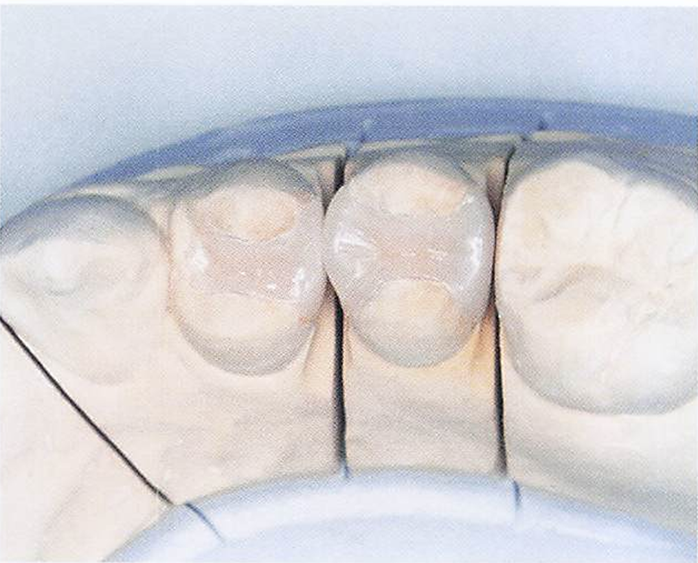

ある患者の上顎前歯の形態を模式図に示す。この患者の胎児期に母親の罹患が疑われるのはどれか。1つ選べ。